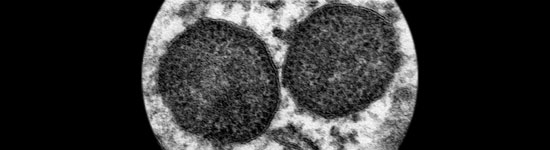

Figura 1. Microfotografía electrónica de dos cuerpos de inclusión en el citoplasma de un macrófago, que incluyen un muy elevado número de partículas de circovirus porcino tipo 2.

Aumento original: 150.000x

Carolina Rodríguez-Cariño, CReSA

El circovirus porcino tipo 2 en un agente vírico de 17 nm de diámetro, uno de los más pequeños entre los virus animales (Fig. 1). Presenta una organización estructural relativamente simple: virus sin envuelta, con una cápside formada mayoritariamente por una sola proteína (proteína Cap o producto del fragmento de lectura abierto 2 [ORF2]), y una cadena simple de ADN de aproximadamente 1767-68 nucleótidos. Este genoma también codifica por proteínas involucradas en la replicación vírica (Rep y Rep’, productos del ORF1). Existiría un ORF3 que se especula podría codificar una proteína con capacidad apoptótica; no obstante, la función de esta proteína no está clara actualmente. Es un virus altamente resistente y, por definición, de difícil eliminación con el uso de desinfectantes. Entre ellos, se consideran de utilidad para disminuir la carga vírica in vitro a la clorhexidina, formaldehídos, iodina y lejía.